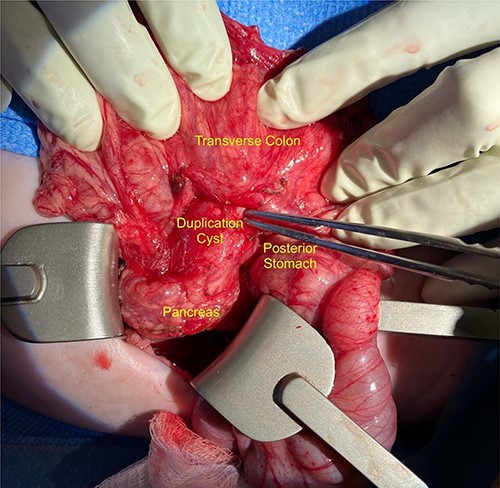

We noted that the patient had an annular pancreas; there was pancreatic tissue around D2 with no evidence of stenosis. There were dense adhesions between the posterior wall of the stomach and this mass, which was essentially embedded within the head of the pancreas and closely positioned but separate from the medial wall of D1 and posterior stomach. There was scarred inflammation extending along the transverse mesocolon, but no true fistula was seen (Fig. 2). There was no evidence of a connection to the pancreatic duct. An intraoperative ultrasound revealed a thick-walled cyst; the fluid in the cyst was of low density with areas of mucous debris dependently (Fig. 3).

Intraoperative image showing the duplication cyst in relation to surrounding organs, and the inflammatory tissue extending from the mass to the colon (at the tip of the forceps).